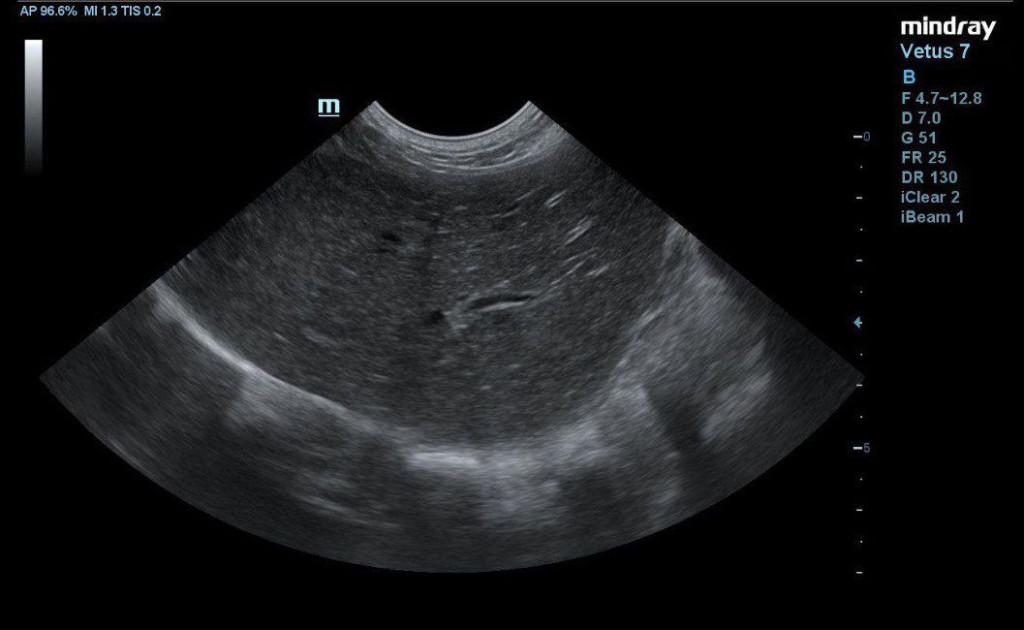

- пониженная эхогенность печени с однородной эхоструктурой и усиленным сосудистым рисунком, что может свидетельствовать о гепатопатии (рис. 2);